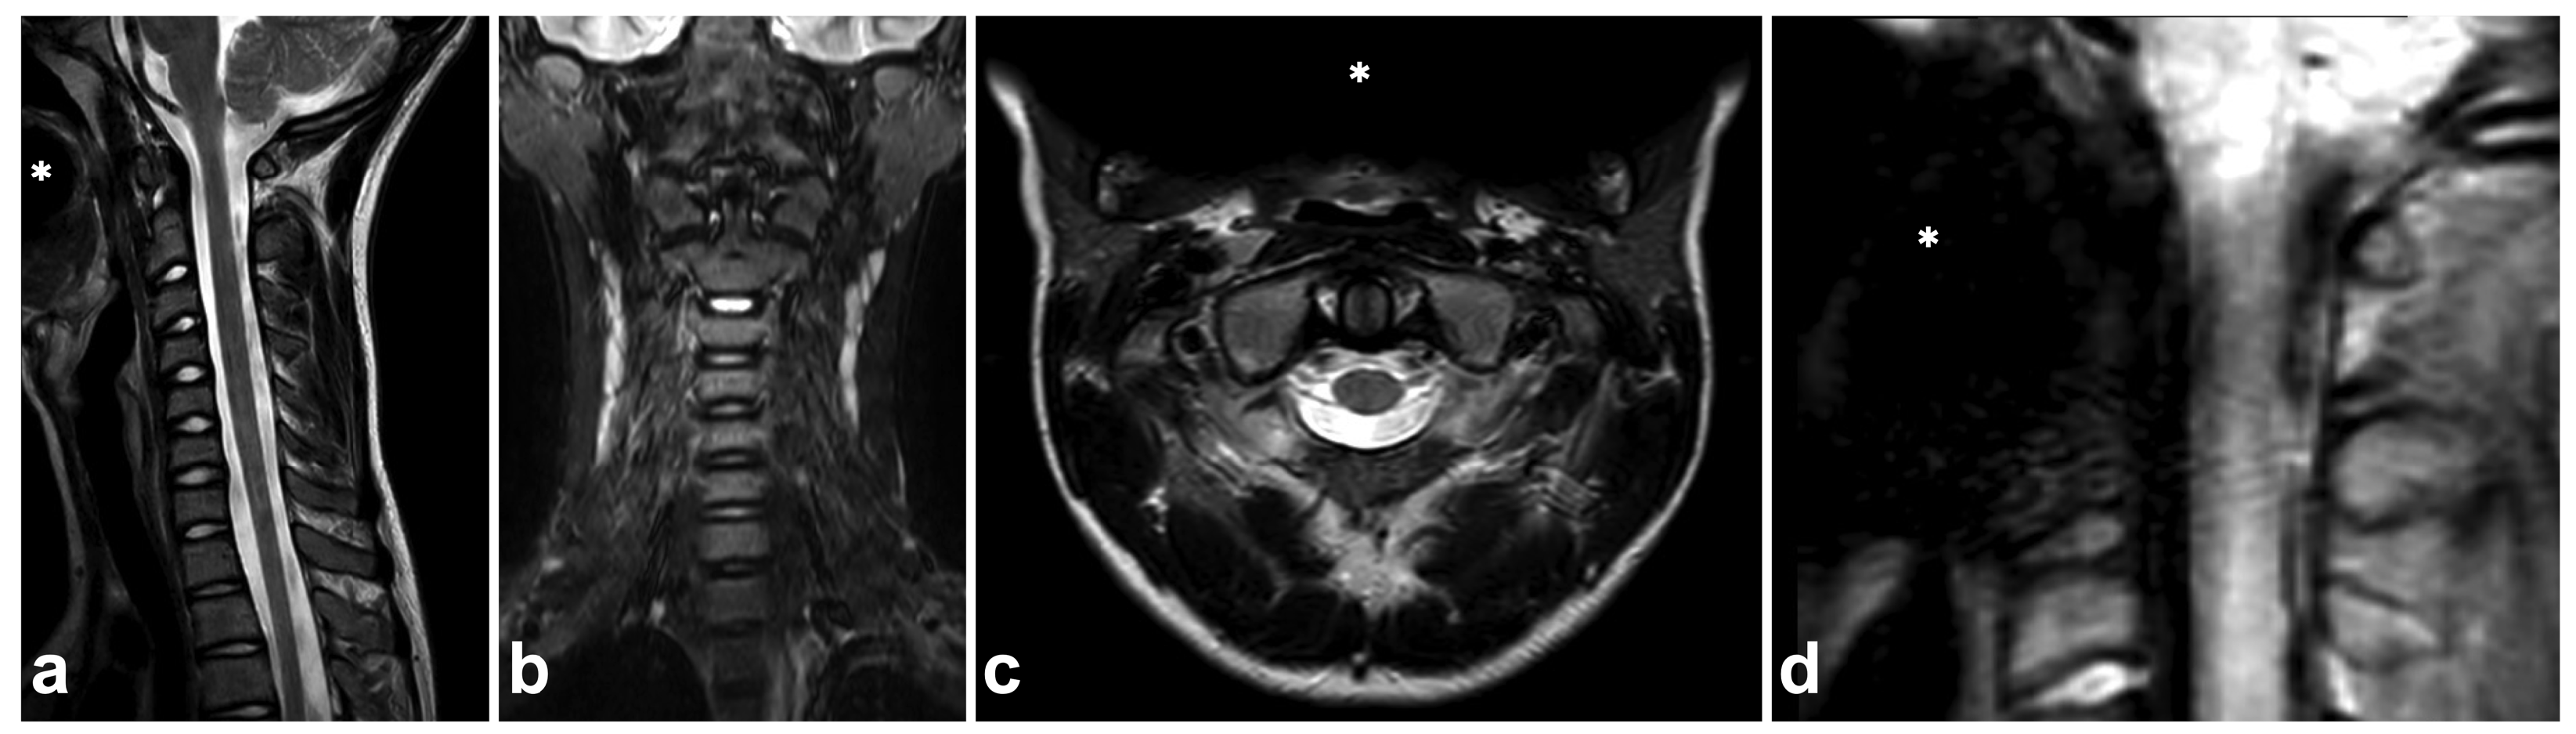

7.7. Metal-Induced Artifacts

Compared to the adult population, ferromagnetic implants and other foreign bodies in the spinal region are uncommon among children. Dental braces are often seen, but, unlike brain MRI, they seldom cause significant challenges in spinal imaging. Braces inflict susceptibility artifacts, but the extent of the artifact is usually limited outside the area of interest (Figure 23). Naturally, for safety reasons, information about any ferromagnetic foreign body within the patient must be ensured, and the possible effects on MRI safety and image quality must be assessed [94,95].

Figure 23.

(a) Sagittal T2-weighted. (b) Coronal STIR. (c) Axial T2-weighted. (d) Sagittal PD-weighted, dedicated small-FOV upper cervical spine series. A 12-year-old male, flexion and axial load to the cervical spine in a trampoline accident. The patient wears braces. Metal-induced artifacts (asterisks) are seen, but they disturb assessments of the spine only in small-FOV PD-weighted imaging.